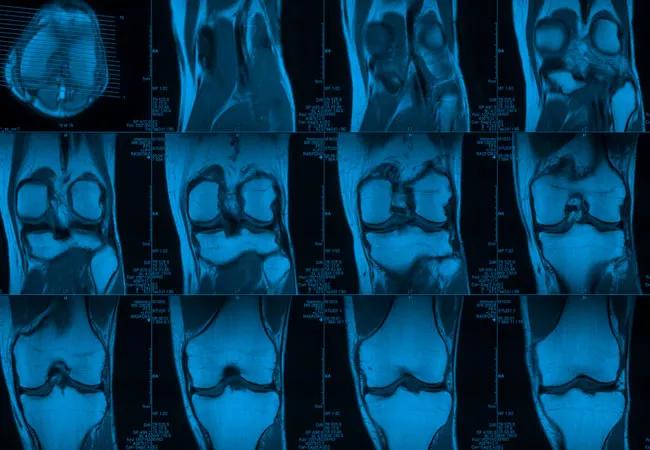

Multiple MRI scans of knees

February 12, 2024/Orthopaedics/Arthritis

Arthritis Foundation and Cleveland Clinic to Build National Osteoarthritis Imaging Center

Center will coordinate, interpret and archive imaging data for all multicenter trials conducted by the foundation’s Osteoarthritis Clinical Trial Network

ACL injuries are one of the most common, and severe, knee injuries, and are usually reconstructed with surgery. Even after surgery, however, patients are at greater risk for post-traumatic osteoarthritis (PTOA). At this time, it is difficult to accurately predict which patients will develop PTOA several years after the surgery. While earlier studies have focused on short- and mid-term magnetic resonance imaging (MRI) follow-up, long-term soft tissue degeneration of the knee following ACL surgery has not been evaluated.

This multicenter study will add on to the Multicenter Orthopaedic Outcomes Network Study, which followed for 10 years patients who had an ACL reconstruction to determine their risk for PTOA. The new study will utilize an advanced type of MRI known as quantitative MRI, or qMRI, to see damage to the knee earlier than a regular MRI, while it can still be prevented. Nancy Obuchowski, PhDDepartment of Quantitative Health Sciences, helped design this new study.

The qMRI studies will evaluate the cartilage, bone, muscle and other lesions in the surgically reconstructed knees that may be related to osteoarthritis. The goal of the study is to illustrate long-term structural damage and degeneration of the cartilage after the ACL reconstruction to help identify the risk factors for PTOA, as well as ways to prevent them.